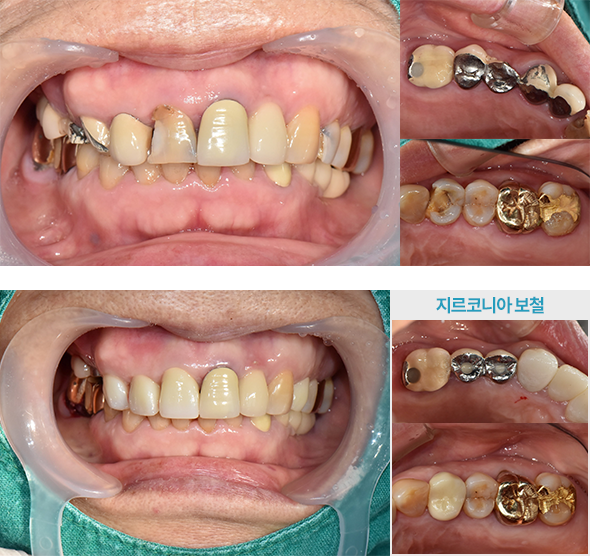

· (임플+지르) 기존 보철물 뜯어내고 임플란트 + 일부 신경치료 후 지르코니아 보철물 진행 case

치료 후 사진은

자세히보기에서 확인하실 수 있습니다.

+ 자세히보기